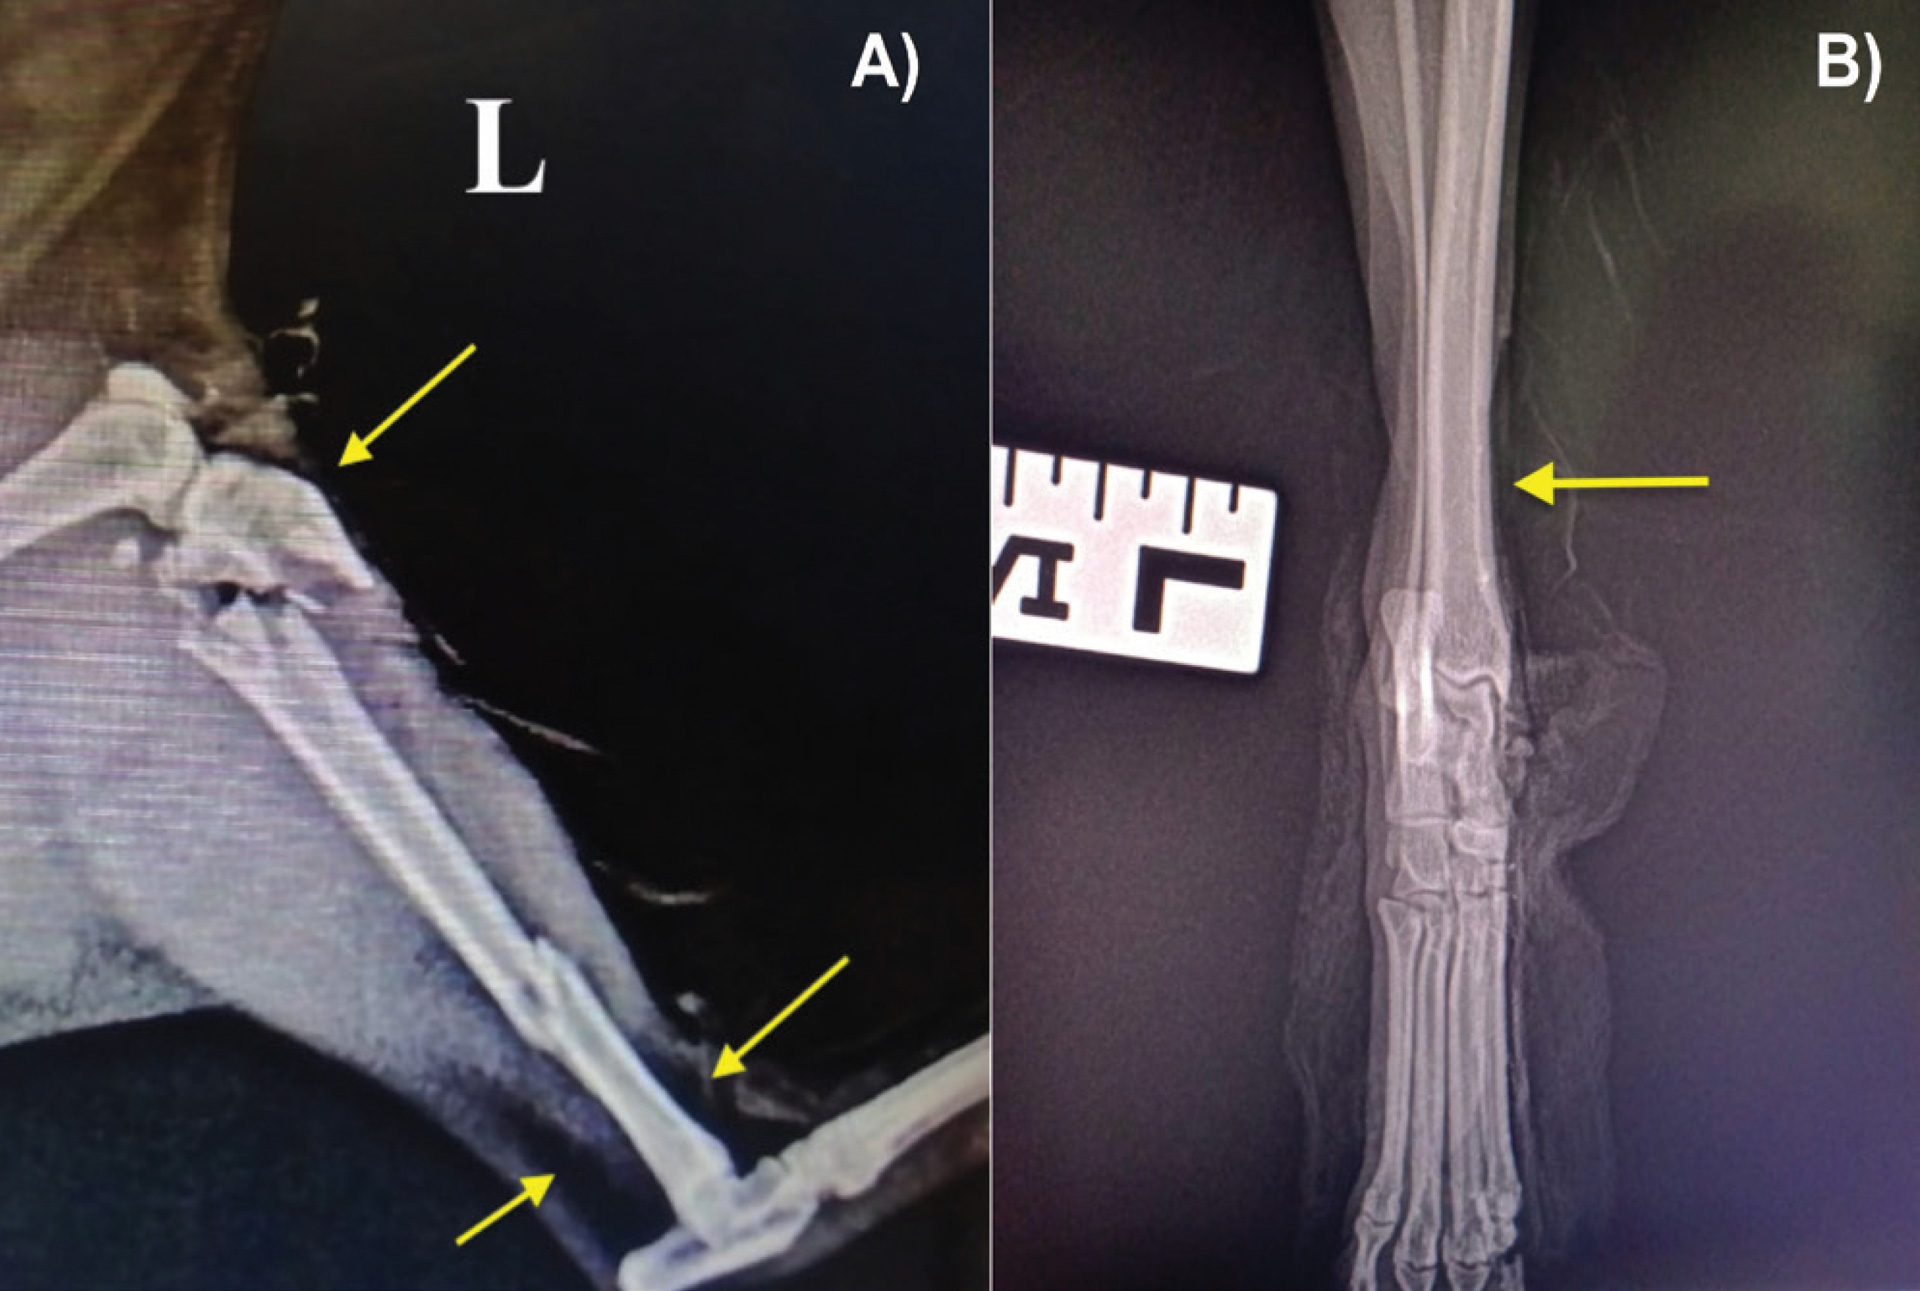

Figure 1: Examples of radiographic appearance of open fractures. A) Highly comminuted fracture in a feline patient affecting the proximal and distal diaphysis of the left tibia following a fall from a third floor. B) Left tibiotarsal mediolateral subluxation (view in neutral position) in a canine patient after a road traffic accident. The yellow arrows indicate gas accumulation under the skin due to soft tissue barrier disruption.

Figure 2: Examples of radiographic appearance of open fractures. A) Caudo-craneal and B) mediolateral radiographs of a comminuted fracture of the mid diaphysis of the right tibia in a five month-old canine patient after a road traffic accident. The yellow arrows indicate gas accumulation under the skin due to soft tissue barrier disruption.